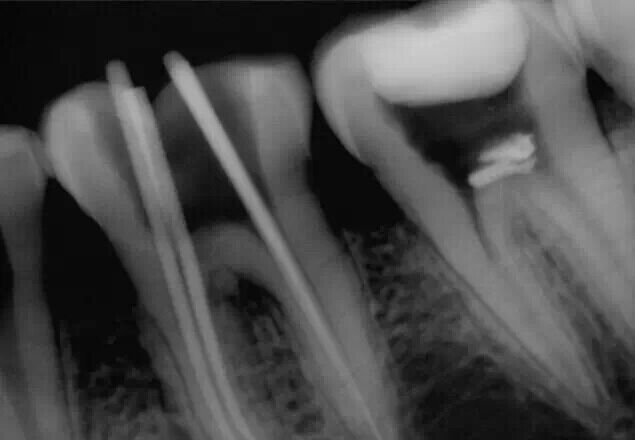

忘記照術(shù)前片了,補(bǔ)一張去腐后的照片。在進(jìn)行根管預(yù)備的時(shí)候D7遠(yuǎn)中出現(xiàn)器械分離

沒辦法只能掏針了,先形成側(cè)方通路,然后用超聲慢慢往出震。